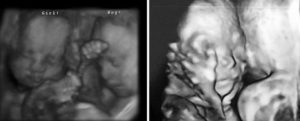

20 неделя беременности двойней: что происходит с детьми

Головки ваших малышей сейчас размером с куриное яйцо.

Для защиты кожных покровов от воздействия амниотической жидкости, тела малышей покрыты пушком лануго и первородной смазкой белого цвета.

- Окружность головок: 178 мм

- Окружность животиков: 158 мм

- Длина бедренных костей: 34 мм

- Вес: 330 г

- Рост: 23,9 см